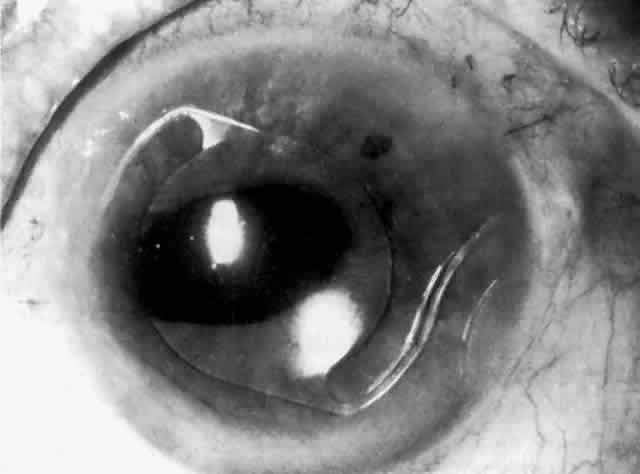

IOL-related inflammation is more commonly associated with some styles of lens implants than with others. Position of the lens or foreign material deposited on the lens during manufacture can also account for persistent inflammation. When the inflammation is associated with hyphema, it is termed UGH syndrome, which involves the triad of uveitis, glaucoma, and hyphema. UGH syndrome occurred more frequently in the 1970s, when iris-fixed lenses were commonly used.66,67 Today it is more often associated with anterior chamber lenses and is less likely to occur with posterior chamber lenses, although this has been reported.68,69 The mechanism is believed to be contact of the surface of the lens with the iris, causing mechanical irritation that may be enhanced by a poorly positioned or mobile lens implant. The loose posterior chamber lens may initially exhibit release of pigment due to friction on the posterior surface of the iris (pseudopigmentary glaucoma). This “windshield-wiper” effect alone can produce enough pigment to provoke an increase in IOP; however, it is the erosion into vascular tissue that results in hemorrhage, hyphema, and inflammation (Figs. 4 and 5).

Fig. 4. Posterior chamber lens implant with prolene haptics, with the patient's head in the primary position.

Fig. 5. Same posterior chamber lens implant as in Figure 4, but with the patient's head tilted, demonstrating mobility of the lens in the posterior chamber. (Courtesy of Dr. R. K. Parrish, Miami, FL.)

Persistent Release of Pigment: Pseudopigmentary Glaucoma

As mentioned in the Persistent Inflammation section, pseudopigmentary glaucoma is in many ways similar to the persistent inflammation that results from an IOL implant. The mechanism is believed to be contact of the surface of the lens with the iris. In persistent inflammation and UGH syndrome, typically either an anterior chamber lens or an iris-fixed lens is the culprit. With respect to pseudopigmentary glaucoma, however, the lens used is more likely to be a posterior chamber lens with the haptics (either one or both) positioned in the sulcus. In this way, the pigmented surface of the iris moves back and forth across the edge of the IOL, promoting release of pigment into the anterior chamber (see Figs. 4 and 5). The mechanism of IOP elevation is outflow obstruction from the excessive amounts of pigment granules and cell debris in the trabecular meshwork.